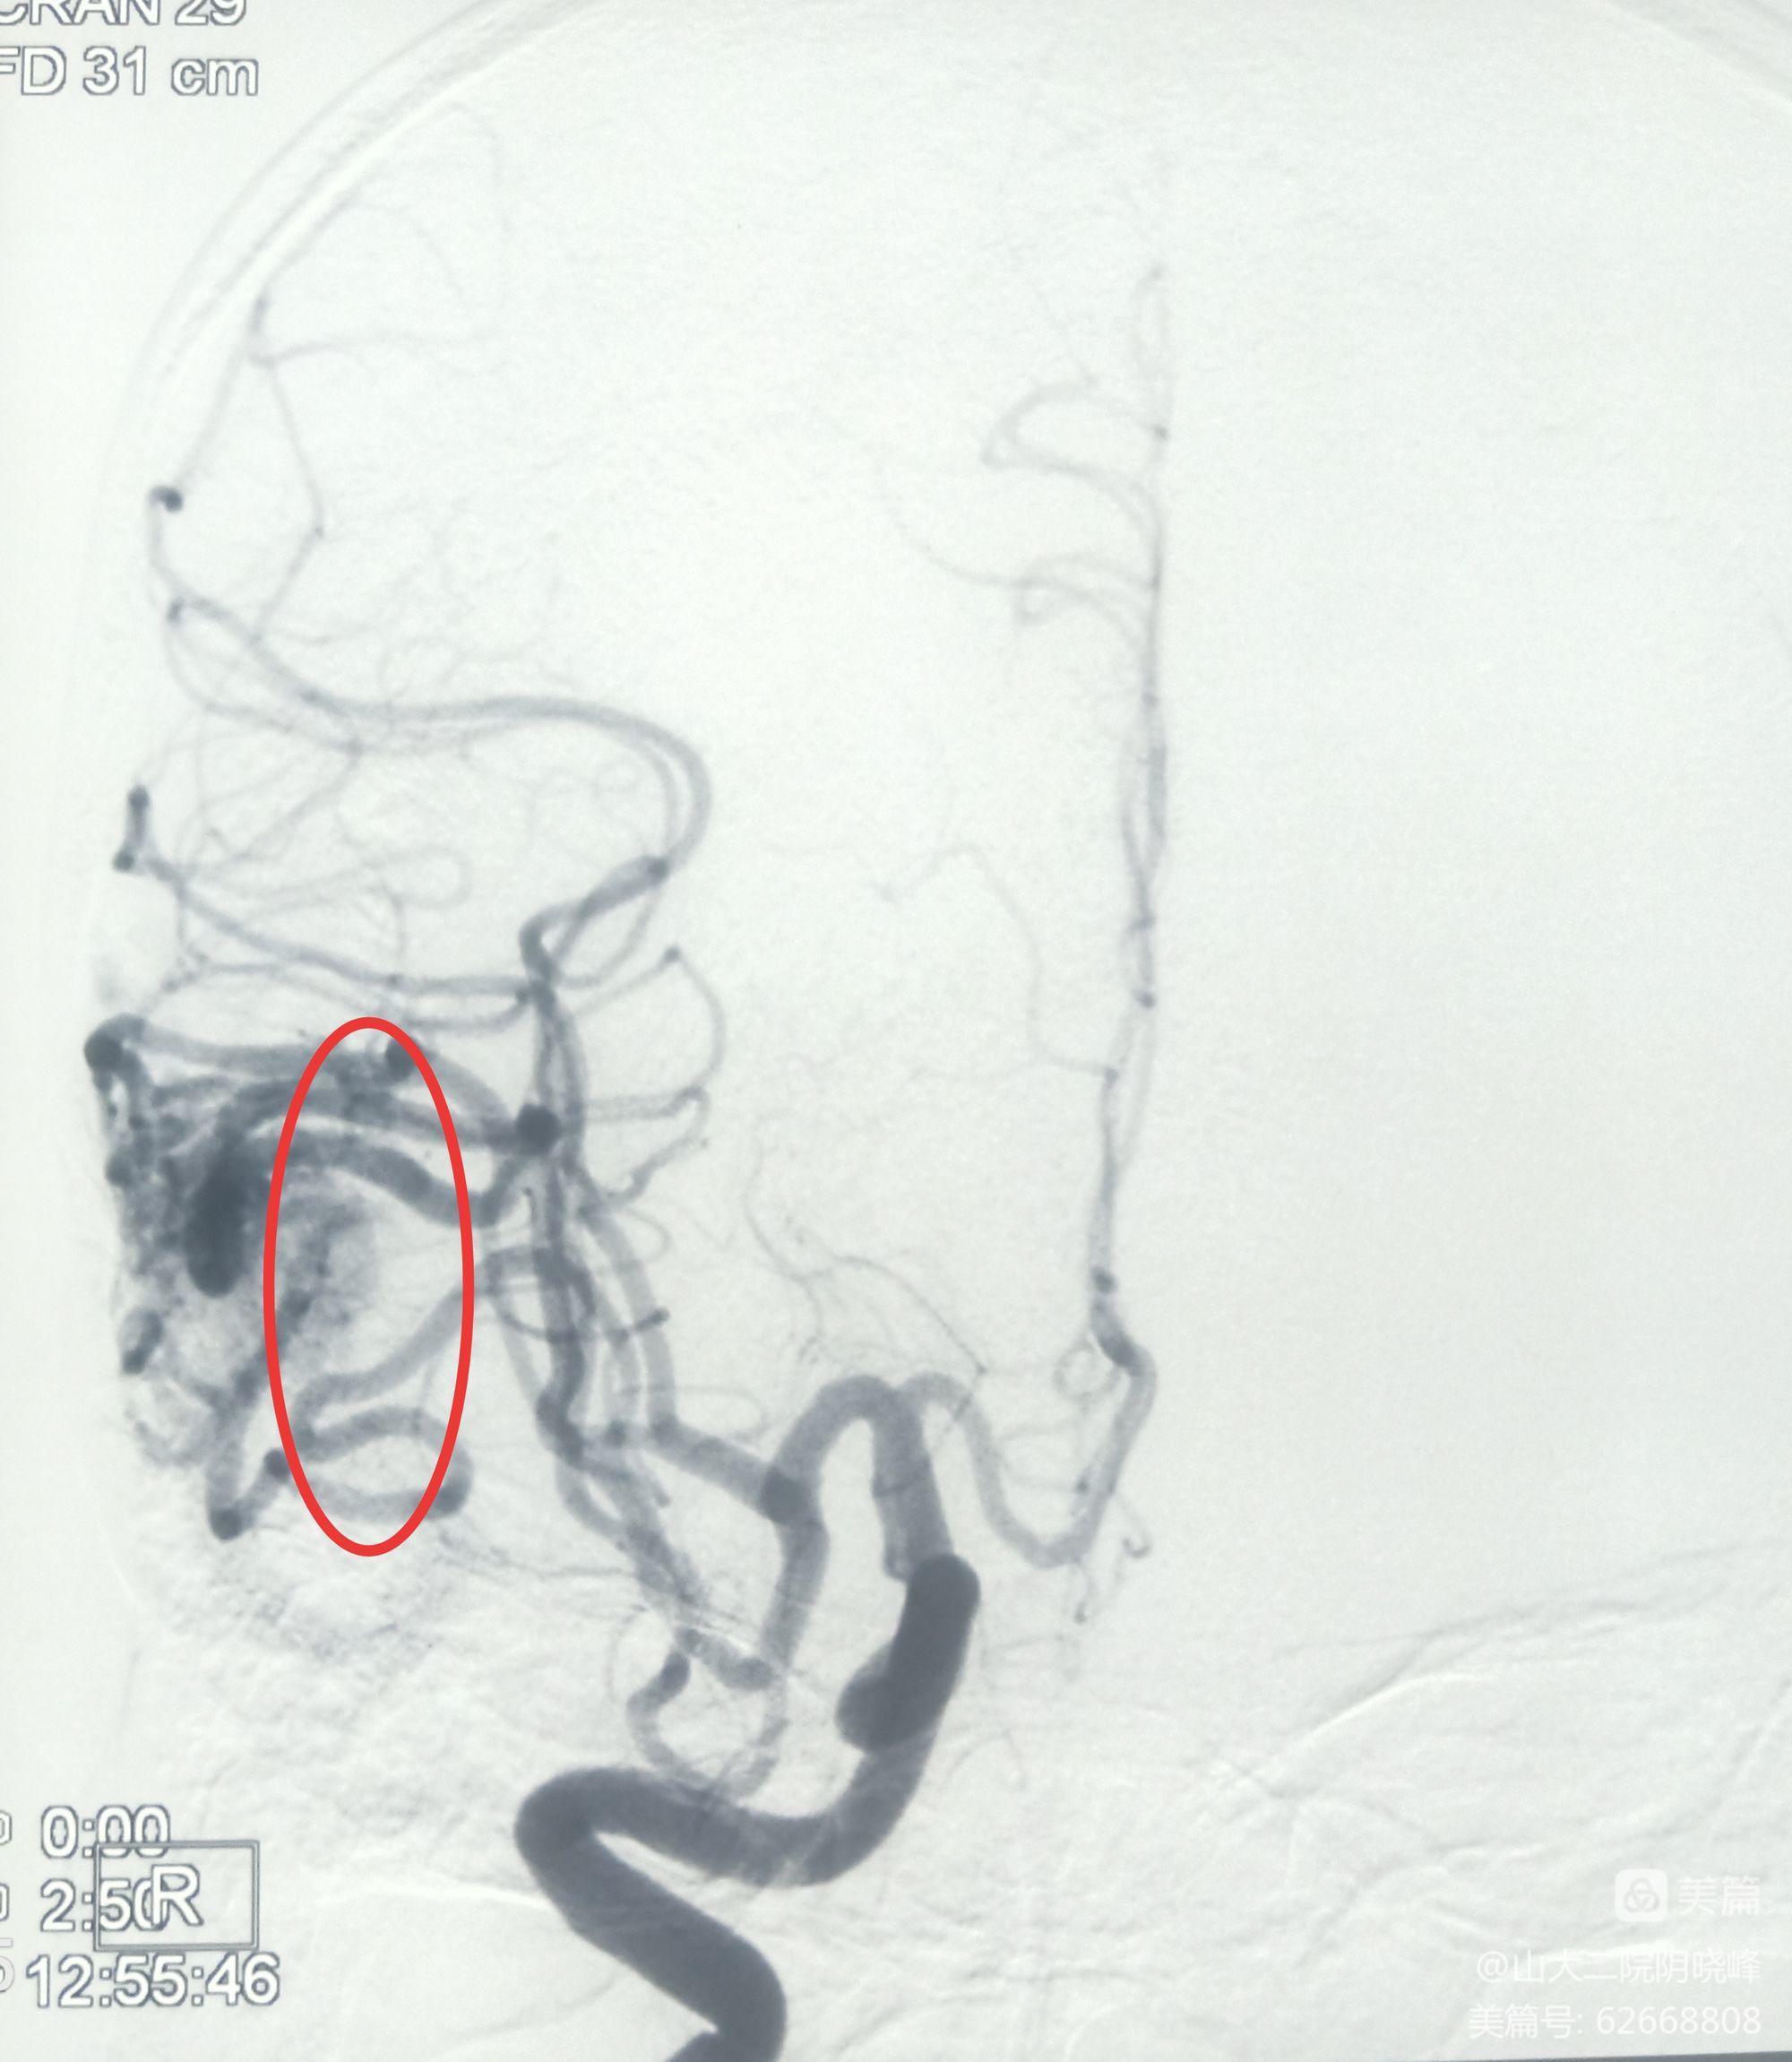

术前DSA明确供血动脉

术前DSA明确引流静脉

术前DSA

术中DSA复查造影:未见动静脉畸形显影,证实病灶全切。